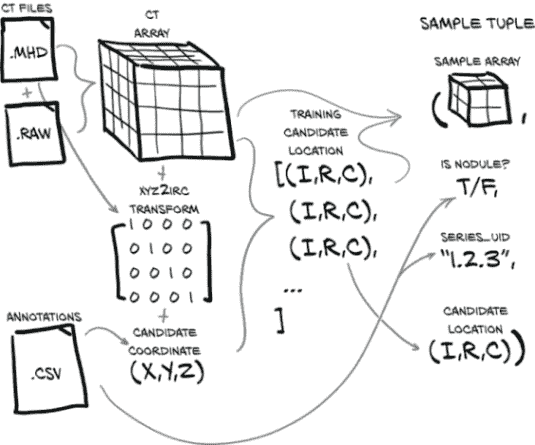

我们的目标是能够根据我们的原始 CT 扫描数据和这些 CT 的注释列表生成一个训练样本。这听起来可能很简单,但在我们加载、处理和提取我们感兴趣的数据之前,需要发生很多事情。图 10.2 展示了我们需要做的工作,将我们的原始数据转换为训练样本。幸运的是,在上一章中,我们已经对我们的数据有了一些理解,但在这方面我们还有更多工作要做。

图 10.2 制作样本元组所需的数据转换。这些样本元组将作为我们模型训练例程的输入。

我们的Ct类将消耗这两个文件并生成 3D 数组,以及转换矩阵,将患者坐标系(我们将在第 10.6 节中更详细地讨论)转换为数组所需的索引、行、列坐标(这些坐标在图中显示为(I,R,C),在代码中用_irc变量后缀表示)。现在不要为所有这些细节担心;只需记住,在我们应用这些坐标到我们的 CT 数据之前,我们需要进行一些坐标系转换。我们将根据需要探讨细节。

我们还将加载 LUNA 提供的注释数据,这将为我们提供一个结节坐标列表,每个坐标都有一个恶性标志,以及相关 CT 扫描的系列 UID。通过将结节坐标与坐标系转换信息结合起来,我们得到了我们结节中心的体素的索引、行和列。

使用(I,R,C)坐标,我们可以裁剪我们的 CT 数据的一个小的 3D 切片作为我们模型的输入。除了这个 3D 样本数组,我们必须构建我们的训练样本元组的其余部分,其中将包括样本数组、结节状态标志、系列 UID 以及该样本在结节候选 CT 列表中的索引。这个样本元组正是 PyTorch 从我们的Dataset子类中期望的,并代表了我们从原始原始数据到 PyTorch 张量的标准结构的桥梁的最后部分。